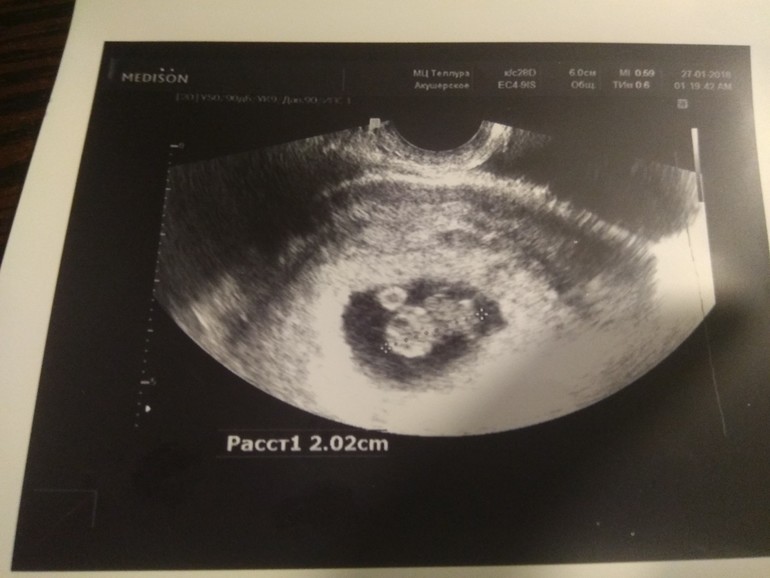

3 января 2018. Попала в больницу с подозрением на внематочную. Праздники, узи необходимо ждать 5 января, а пока папаверин, дюфастон и ходи до туалета по коридору, только медленно. Сильнейшие боли в правой части живота не дают спать ночами.

5 января 2018. УЗИ. Сижу на лавочке. Кабинет напротив. Только не трясись, пожалуйста… Захожу. Ужасно злая дама командует мне лечь на кушетку и постелить полотенце. Повинуюсь. Плачу. Сейчас я хочу заткнуть уши. «Поздравляю» - говорит узистка. Очень смешно, а когда на операцию то? «Сердцебиение 120 ударов». Плачу. И как его вырезать… У него же сердце стучит… Спрашиваю тоже самое, что и в голове. Узистка смеется, а мне еще хуже становится. Дьяволы. Дает мне фотография кружочка и отправляет обратно в отделение. По дороге решила прочитать заключение. Маточная беременность, срок 5-6 недель. ЧЕГО? Муж сидел в приемном и ждал. Так мы никогда не плакали. Вдвоем, навзрыд. Долго.